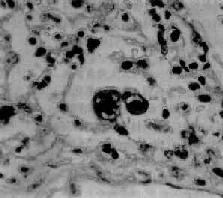

图9-21 腺病毒肺炎 图中央可见肿大肺泡上皮细胞中的核内包含体 有些混合感染,如麻疹病毒合并腺病毒感染,特别是又继发细菌感染的病毒性肺炎,病变更为严重,肺炎病灶可呈小叶性、节段性或大叶性分布。支气管和肺组织明显坏死、出血,并可混杂化脓性病变,从而掩盖了病毒性肺炎原来的病变特征。 (三)支原体肺炎 支原体肺炎(mycoplasmal pneumonia)是由肺炎支原体(mycoplasma pneumoniae)引起的一种间质性肺炎。支原体系介于细菌和病毒之间的微生物,共有30余种,其中多种可寄生于人体,但不致病,仅有肺炎支原体能引起呼吸道疾病。各种肺炎中约有5%~10%乃由肺炎支原体引起。主要经飞沫感染,秋、冬季节发病较多,儿童和青年发病率较高,通常为散发性,偶尔流行。患者起病较急,多有发热、头痛、咽痛及剧烈咳嗽(常为干性呛咳)等症状。胸部检查,可闻干、湿啰音。X线检查,肺部呈段性分布的纹理增加及网织状阴影。白细胞计数有轻度升高,淋巴细胞和单核细胞增多,痰、鼻分泌物及咽喉拭子能培养出肺炎支原体。 病理变化 肺炎支原体感染可引起整个呼吸道的炎症。肺部病变常仅累及一个肺叶,以下叶多见。病变主要发生于肺间质,病灶呈段性分布,暗红色,切面可有少量红色泡沫状液体溢出。气管或支气管腔内也可见粘液性渗出物。胸膜光滑。镜下,病变区域肺泡间隔明显增宽,有大量淋巴细胞、浆细胞和单核细胞浸润,肺泡腔内无渗出物或仅有少量混有单核细胞的浆液性渗出液。小支气管和细支气管壁及其周围组织也常有炎性细胞浸润。重症病例,上皮亦可坏死脱落,往往伴有中性粒细胞浸润。支原体肺炎预后良好。死亡率在0.1%~1%之间。 三、职业性肺疾病 在职业活动、特别是生产过程中,因长期吸入有害粉尘,引起以肺广泛纤维化为主要病变的疾病,统称尘肺(pneumoconiosis)。尘肺是我国一种法定职业病。属职业性尘肺的病种较多,按粉尘的化学性质可将其分为无机尘肺和有机尘肺两大类。无机尘肺中常见的有矽肺、煤工尘肺、石棉肺等。有机尘肺是因吸入各种有机尘埃,最常见的是由霉菌的代谢产物或动物性蛋白质引起的尘肺,如农民肺、蔗尘肺、蘑菇肺、麦芽肺和饲禽者肺等。尘肺对健康危害极大,关键在于预防。改革不合理的生产过程,建立粉尘监测制度,切实落实综合防尘措施。不接触粉尘或减少吸入粉尘的机会,对于粉尘作业工人定期体检,做到早期检查、早期诊断,对已确诊为尘肺患者及早调离粉尘作业,并进行必要的治疗,完全可以控制和减少尘肺的发病率。 (责任编辑:泉水) |

图9-19 支气管肺炎 图中见灶状实变的肺组织,肺泡内充满以中性粒细胞为主的炎性渗出物;病灶中有发炎的细支气管 并发症 小叶性肺炎发生并发症的危险性比大叶性肺炎大得多。可并发心力衰竭、呼吸衰竭、脓毒败血症、肺脓肿及脓胸等。支气管破坏较重且病程较长者,可导致支气管扩张。 临床病理联系 因小叶性肺炎多为其他疾病的并发症,其临床症状常为原发性疾病所掩盖。由于支气管粘膜的炎症刺激而引起咳嗽,痰呈粘液脓性。因病变常呈灶性散布,肺实变体征一般不明显。病变区细支管和肺泡内含有渗出物,听诊可闻湿啰音。X线检查,可见肺野内散在不规则小片状或斑点状模糊阴影。本病发现及时,治疗得当,肺内渗出物可完全吸收而痊愈。但在幼儿,年老体弱者,特别是并发于其他严重疾病时,预后大多不良。 (二)病毒性肺炎 病毒性肺炎(viral pneumonia)常常是因上呼吸道病毒感染向下蔓延所致。患者多为儿童,症状轻、重不等,但婴幼儿和老年患者病情较重。一般多为散发,偶可酿成流行。引起肺炎的病毒种类较多,常见的是流感病毒、还有呼吸道合胞病毒、腺病毒、副流感病毒、麻疹病毒、巨细胞病毒等等,也可由一种以上病毒混合感染并可继发细菌感染。病毒性肺炎的病情、病变类型及其严重程度常有很大差别。 病理变化 早期或轻型病毒性肺炎表现为间质性肺炎,炎症从支气管、细支气管开始,沿肺间质发展,支气管、细支气管壁及其周围、小叶间隔以及肺泡壁等肺间质充血、水肿,有一些淋巴细胞和单核细胞浸润,肺泡壁明显增宽(图9-20)。肺泡腔内一般无渗出物或仅有少量浆液。病变较重者,肺泡也可受累,出现由浆液、少量纤维蛋白、红细胞及巨噬细胞组成的炎性渗出物,甚至可发生组织坏死。有些病毒性肺炎(如流感病毒肺炎,麻疹病毒肺炎、腺病毒肺炎等)肺泡腔内渗出较明显,渗出物浓缩凝结成一层红染的膜样物贴附于肺泡内表面,即透明膜形成。支气管上皮的肺泡上皮也可增生,甚至形成多核巨细胞。麻疹病毒肺炎的病变特点为在间质性肺炎的基础上,肺泡壁上有透明膜形成,并有较多的多核巨细胞(巨细胞肺炎),在增生的上皮细胞和多核巨细胞的胞浆内和胞核内可检见病毒包含体。病毒包含体常呈球形,约红细胞大小,呈嗜酸性染色,均质或细颗粒状,其周围常有一清晰的透明晕。其他一些病毒性肺炎也可在增生的支气管上皮、支气管粘液腺上皮或肺泡上皮细胞内检见病毒包含体。如腺病毒肺炎可在增生的上皮细胞核内(图9-21),呼吸道合胞病毒肺炎可在增生的上皮细胞胞浆内,巨细胞病毒肺炎也可在增生的上皮细胞核内检见病毒包含体。检见包含体是病理组织学诊断病毒性肺炎的重要依据。